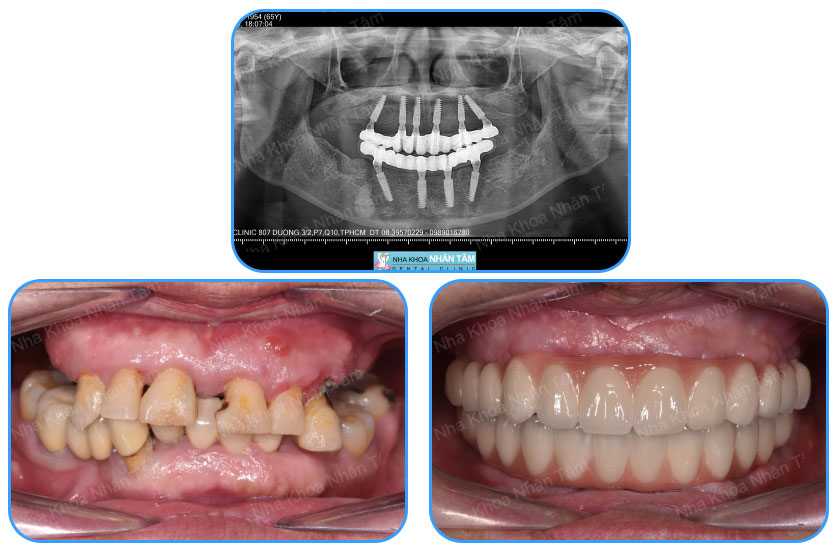

Implant All on 4 - All on 6 là phương pháp có thể phục hình cùng lúc 12 - 14 răng cố định trên cùng một hàm mà chỉ cần cắm 4 hoặc 6 trụ implant (quá trình cắm trụ Implant sẽ được chia thành nhiều lần, mỗi lần chỉ cắm 2 trụ Implant để đảm bảo an toàn cho khách hàng).

Với kỹ thuật này, Bác sĩ sẽ chỉ cần cắm 4 trụ implant trên một hàm, bao gồm 2 trụ implant phía trước cấy thẳng và 2 trụ implant phía sau cấy nghiêng với góc nghiêng tối đa 45 độ (quá trình cắm trụ Implant sẽ được chia thành 2 lần, mỗi lần cắm 2 trụ Implant để đảm bảo an toàn cho khách hàng).

Bên cạnh 4 trụ implant như kỹ thuật All On 4, việc thêm 2 trụ implant ở vùng răng sau sẽ nâng đỡ tốt hơn, vững chắc hơn (quá trình cắm trụ Implant sẽ được chia thành nhiều lần cắm, mỗi lần cắm 2 trụ Implant để đảm bảo an toàn). Sau phẫu thuật, chức năng ăn nhai được đảm bảo và bạn cũng không phải lo lắng vấn đề tiêu xương.

Với kỹ thuật All on 4 và All on 6, sau khi cắm trụ implant, bạn sẽ được đặt hàm tạm tức thì trên implant, để đảm bảo chức năng ăn nhai và thẩm mỹ trong khoảng thời gian chờ phục hình sau cùng.